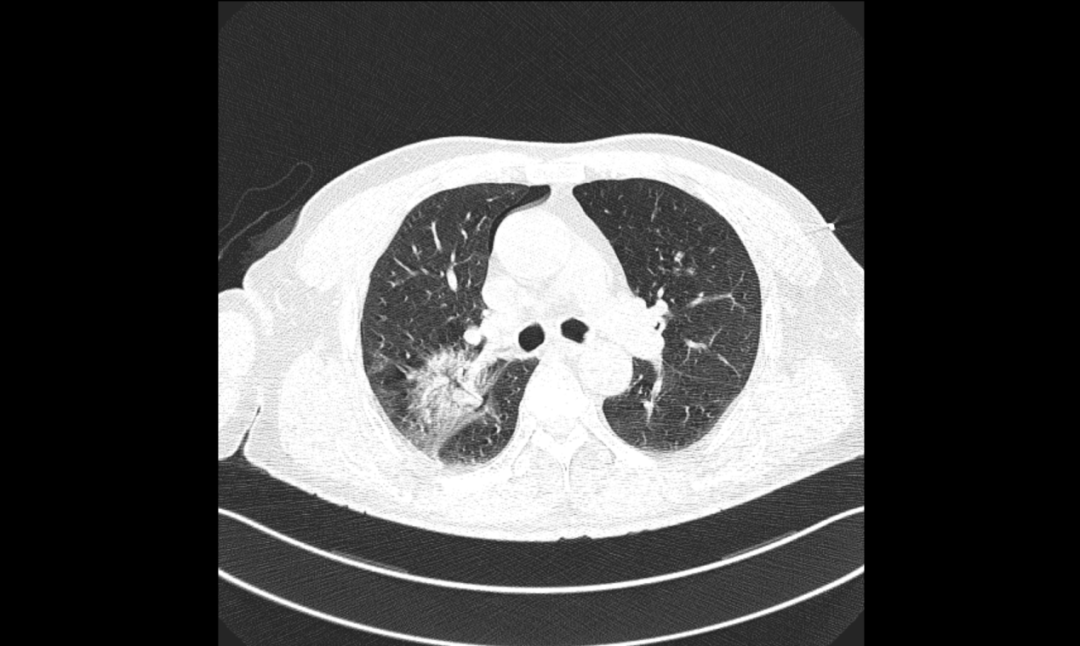

患者李伯,70岁,因“咳嗽、咳痰3月,发现肺部结节20天”入院。患者有慢性阻塞性肺病史,曾因膀胱结石行微创手术治疗,有30余年吸烟史。入院后查体发现双肺呼吸音低,胸部CT显示右肺上叶后段实性结节,有分叶、短毛刺,与血管相连,中度强化,考虑恶性可能性大。

▲胸部增强CT提示右肺结节,恶性可能性大